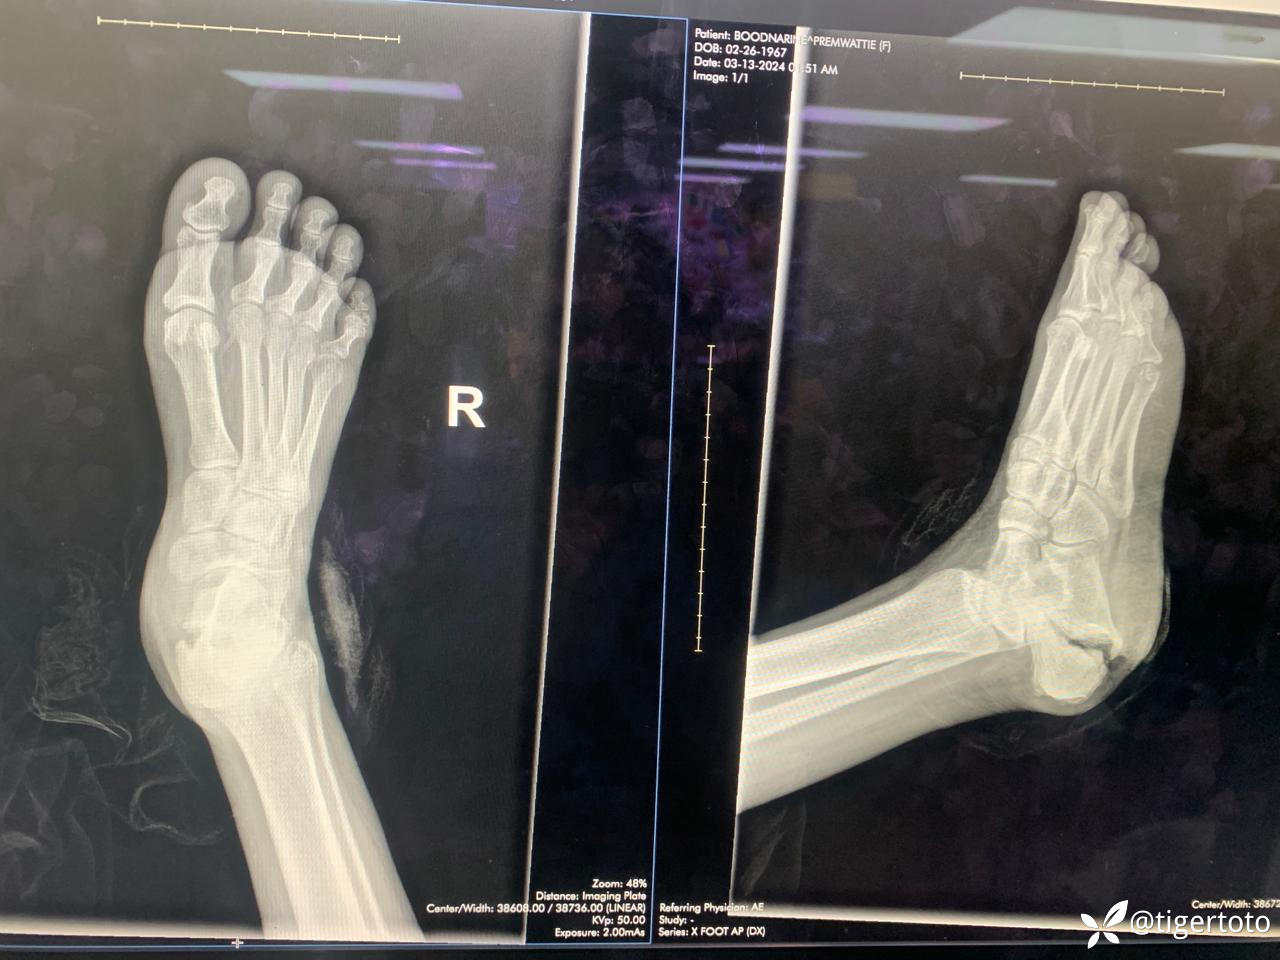

2024年1月,该患者用脚跟踢了别人。一周后,她开始感到同一部位疼痛,于是开始用温水敷——随后出现了水泡。2月,患者到医院就诊,诊断为DM+ HTN,接受换药治疗。病人说伤口正在“改善”,但她无法用脚跟承重。3月8号,她开始注意到脚跟自发性出血,去医院并被告知血管有问题。病人随后被转院接受进一步治疗。

有家族高血压糖尿病史。